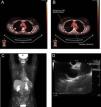

La USE puede muestrear con facilidad los ganglios celíacos a los que no puede accederse por otros métodos de estadificación mediastínica. En un estudio reciente se observó de forma inesperada una elevada incidencia de metástasis en los ganglios celíacos (11%)10. Otros autores ya han señalado la importancia de los ganglios celíacos34,41. La USE también tiene la ventaja de permitir la realización de biopsias de las metástasis suprarrenales izquierdas, si bien resulta más difícil practicar biopsias de la glándula suprarrenal derecha42. Será preciso explorar más profundamente la utilidad de la USE-PAAF en la reestadificación del mediastino en pacientes que hayan recibido quimioterapia y radioterapia para enfermedad N2 (fig. 2). Si la estadificación mediastínica inicial incluye una mediastinoscopia, la mayoría de los cirujanos tratan de evitar su repetición tras la radioterapia. La reestadificación mediante PET y TAC puede ayudar a aportar dianas para la biopsia, pero, como sabemos, es necesario tomar muestras del mediastino incluso cuando la PET es negativa. La USE-PAAF y la USEB-PAAF parecen inclinar claramente la balanza del riesgo-beneficio en estos pacientes43.

Reestadificación con ultrasonografía endoscópica (USE) del cáncer de pulmón no microcítico después de una mediastinoscopia. A: la estadificación inicial con tomografía por emisión de positrones (PET) muestra un nódulo “caliente” en el lóbulo superior derecho (LSD) con un valor de captación estándar de 7,1. B: corte de la exploración con PET para la estadificación inicial, que muestra un elevado grado de avidez por la glucosa en la región subcarinal, indicativo de metástasis en los ganglios linfáticos. C: PET de reestadificación después de la quimioterapia de inducción y radiación, que muestra una reducción de la intensidad de la masa del LSD y ninguna actividad en el mediastino, lo que indica una buena respuesta al tratamiento. D: 2 ganglios linfáticos pequeños en la ventana aortopulmonar (3mm) visibles en la USE; las biopsias guiadas por USE mostraron, sin embargo, cáncer de pulmón no microcítico.